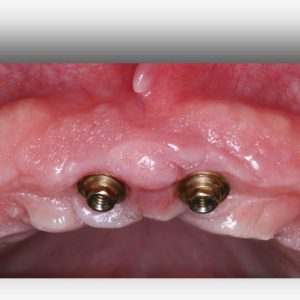

A implantodontia é um procedimento odontológico que envolve a colocação de implantes dentários de titânio no osso maxilar ou mandibular para substituir dentes perdidos. Os implantes proporcionam uma base sólida para a fixação de coroas, pontes ou próteses, restaurando a função mastigatória, estética e saúde bucal do paciente.